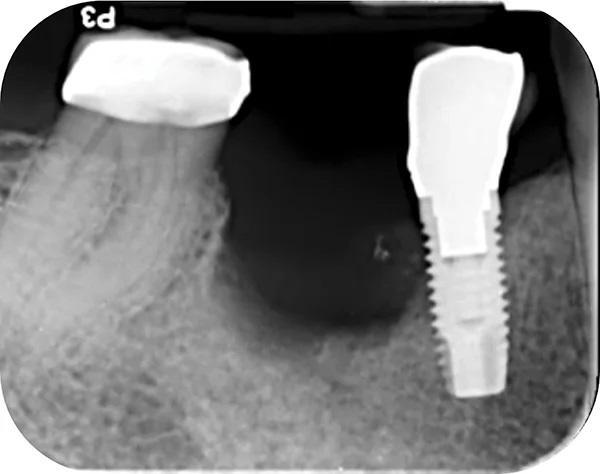

Пациент отрицал наличие вредных привычек к курению табака, а так же наркотических веществ таких как марихуана, либо пристрастия к другим видам наркотиков. Он не смог вспомнить, когда именно ему были удалены все первые премоляры и зубы мудрости по ортодонтическим показаниям, но отметил, что это произошло до имплантации. 2006 году ему были установлены имплантаты № 3, установленных в боковых отделах нижней челюсти для замещения зубов 4.4. и 4.5.. В 2012 году у него был диагностирован периимплантит в области данных имплантатов, однако в то время он не обращался за рекомендованным лечением. Рентгенографическое исследование периапикальной рентгенограммы, сделанной в 2012 году, показало 50% или более потери костной массы вокруг имплантата зуба 4.5., и около 15 % утраты костной ткани вокруг имплантата зуба 4.4 (фото 1). В декабре 2014 года имплантат зуба 4.5. выпал во время обычного акта жевания, из-за чего пациент не стал продолжать лечение. На фото 2 показан образовавшийся дефект альвеолярного отростка через 2 года после отторжения имплантата зуба 4.5.

Фото 2. Демонстрирует прицельный снимок с образовавшимся дефектом альвеолярного отростка через 2 года после отторжения имплантата зуба 4.5